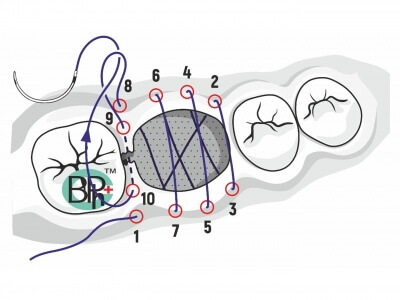

The Piezoelectric Bony Window Osteotomy and Sinus Membrane Elevation: Introduction of a New Technique for Simplification of the Sinus Augmentation Procedure

The Piezoelectric Bony Window Osteotomy and Sinus Membrane Elevation: Introduction of a New

Technique for Simplification of the SinusAugmentation Procedure